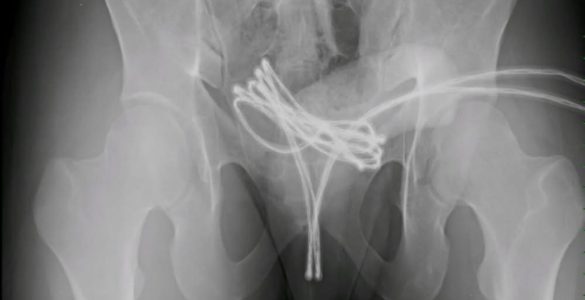

Un caso insolito ha coinvolto un ragazzo inglese di 21 anni, il cui nome non è stato reso pubblico, che è stato ricoverato presso il pronto soccorso dopo un episodio legato a una pratica sessuale rischiosa nota come...